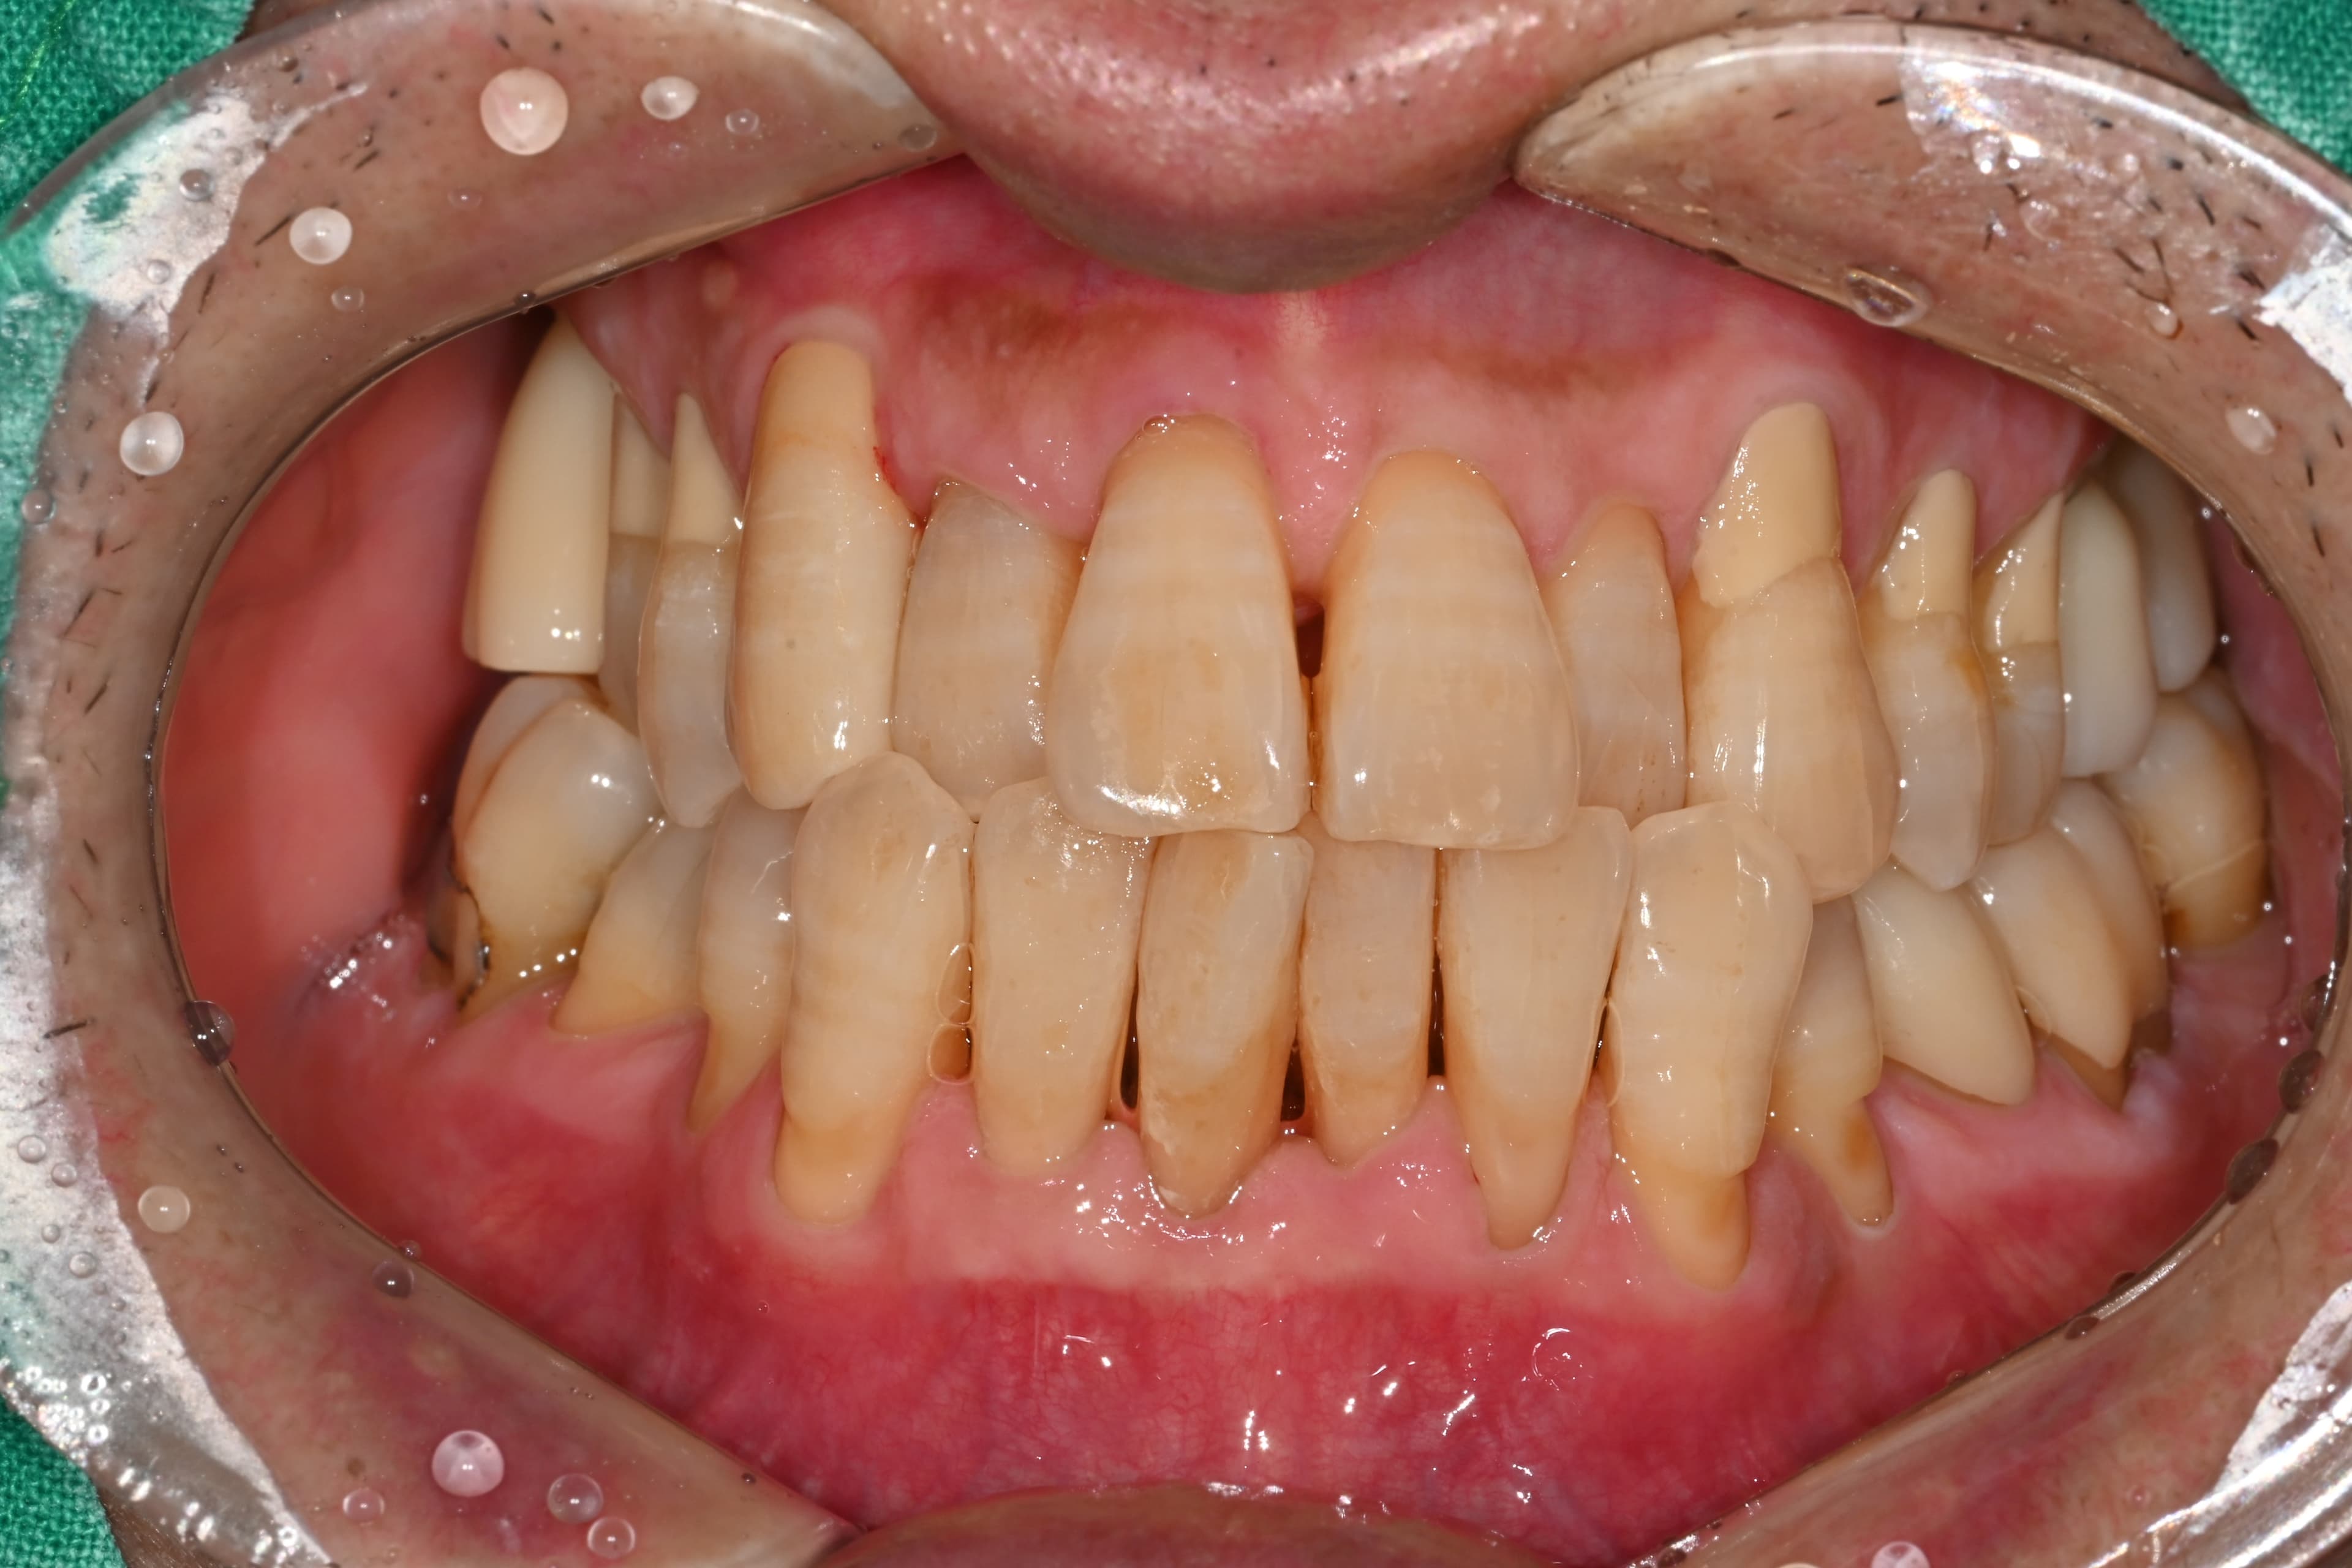

실제 치료 사례

정기적인 잇몸 치료로 임플란트 없이 건강한 치아 유지

"정기적인 관리 덕분에

50대에도 모든 치아가 건강해요"

Before

After

치석과 잇몸 염증이 심했던 상태

정기적인 스케일링과 관리로 건강하게 유지